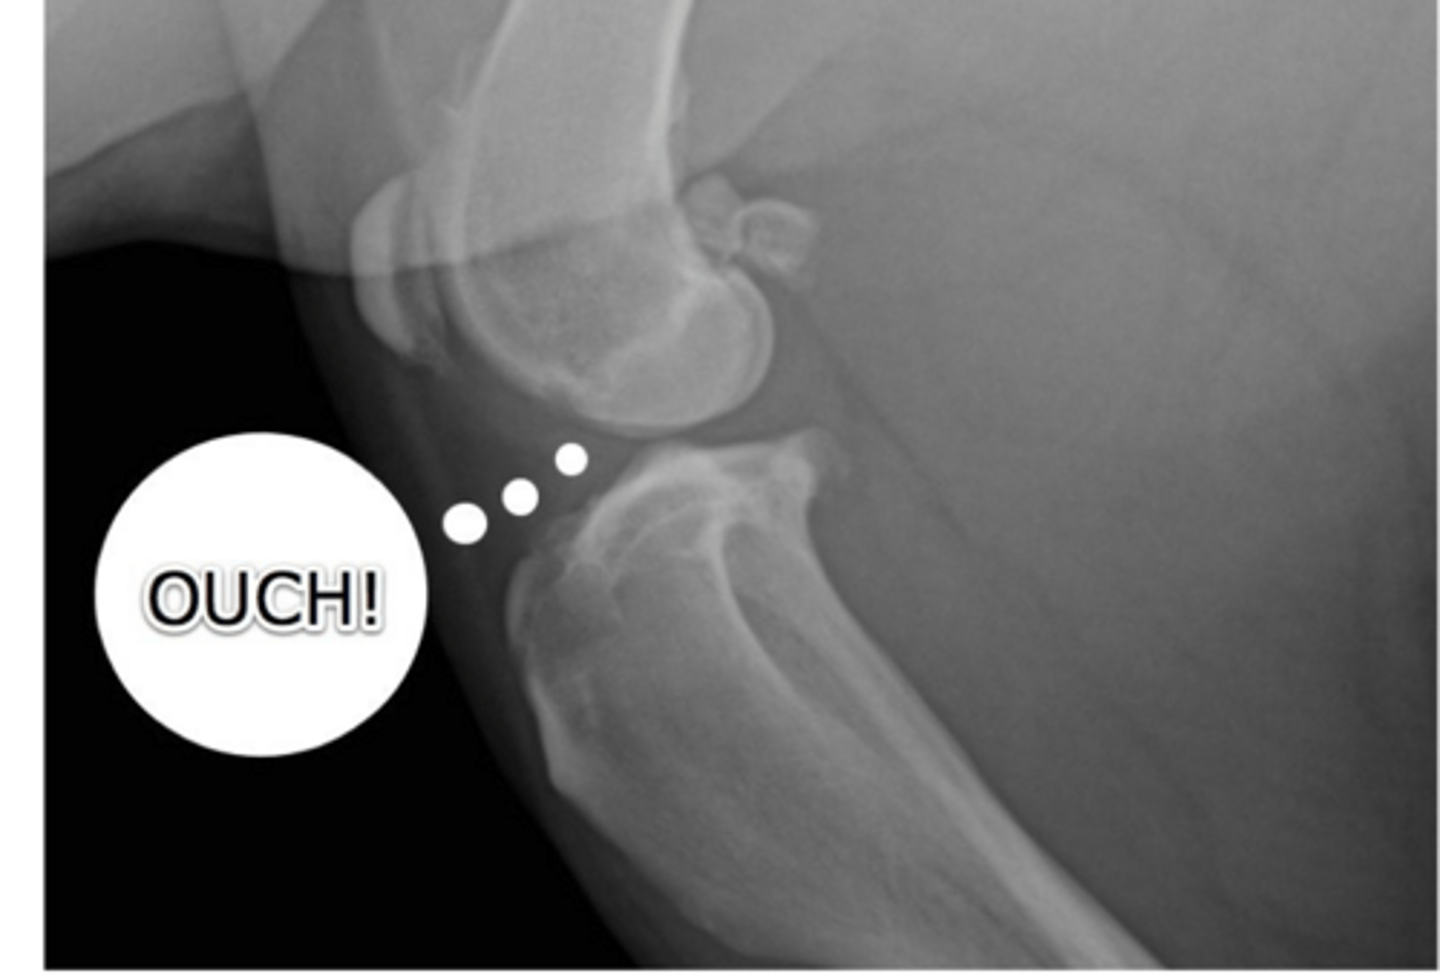

caudal cruciate lig. rupture

what is shown here...

CaCL rupture w/ medial collateral lig. tear